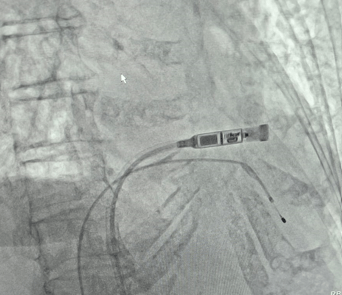

El Hospital Vozandes Quito sigue consolidándose como un referente en innovación y tecnología médica. En un nuevo avance para la cardiología intervencionista, el equipo de especialistas del HVQ, liderado por el Dr. Jorge Luis Arbaiza jefe del servicio de Cardiopulmonar del HVQ y con la colaboración del Dr. Luis Gómez, ha logrado implantar con éxito el primer marcapasos sin cable Micra en nuestra institución.

Este dispositivo representa un cambio revolucionario en el tratamiento de pacientes con problemas de ritmo cardíaco, ya que es el marcapasos más pequeño e innovador del mundo, con un tamaño 93% menor en comparación con los modelos tradicionales. Su diseño mínimamente invasivo permite reducir riesgos, siendo ideal para pacientes con acceso vascular complicado o antecedentes de infecciones con otros dispositivos.